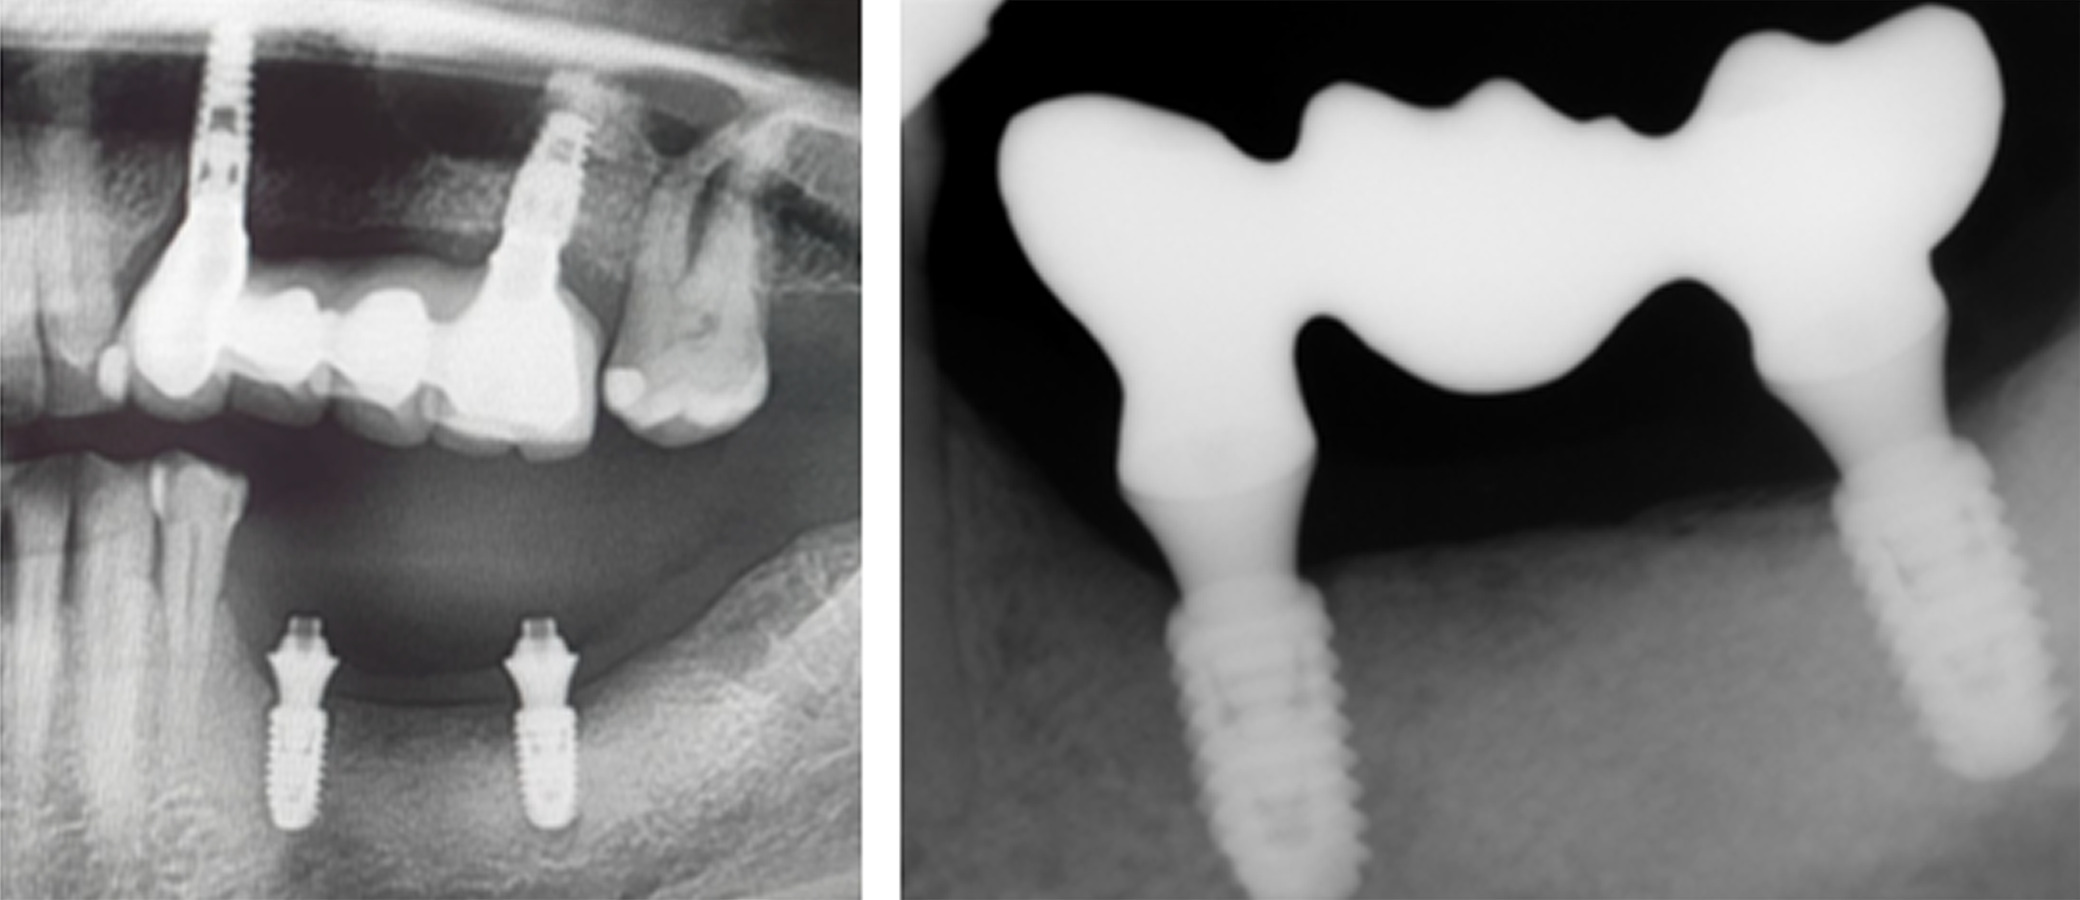

At 6 months postoperative, CT scans showed optimal bone density with mature characteristics and optimal thickness/height for adequate three-dimensional implant placement (Figure 14). Removal of the titanium-reinforced membrane at 3 months postoperative did not appear to have a significant impact on the regenerative process. A full-thickness flap was created for implant placement, revealing a good bone appearance with visible vascularization, rim thickness, and maturation (Figure 15). The implants were placed, achieving favorable primary stability and optimal three-dimensional ridge placement due to the thickness/height achieved from the regenerative procedure (Figure 16). Periapical radiographs following placement of the healing screws confirmed favorable bone-implant interaction (Figure 17). A panoramic radiograph prior to crown placement showed evident hard tissue stability in the regenerated area (Figure 18). Finally, panoramic and periapical radiographs at 24 months postoperative showed healthy, stable bone regeneration and ideal placement of the implants and bridge (Figure 19).

Figure 17. Periapical radiographs following placement of the healing screws showed excellent bone-implant interaction

Figure 18. [Left] Panoramic radiograph prior to crown placement showing evident hard tissue stability in the regenerated area. [Right] Periapical radiograph showing bridge placement from Tooth 35 to 37